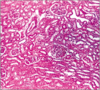

What’s this?

glomerulus

not the endothelium & PCT (fuzzy) etc.